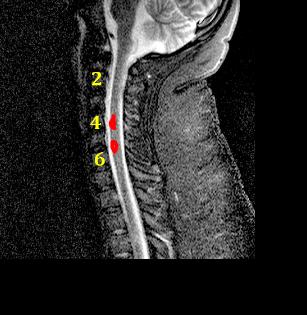

What type of study is this? This is an MR of the cervical spine in the sagittal plane. This is a T2-weighted sequence (CSF is bright), but there is also fat suppression (subcutaneous fat has relatively low signal). How would you describe the abnormal findings? There are at least two areas of abnormal high signal (outined in red) in the cervical cord, between C4 and C6. |